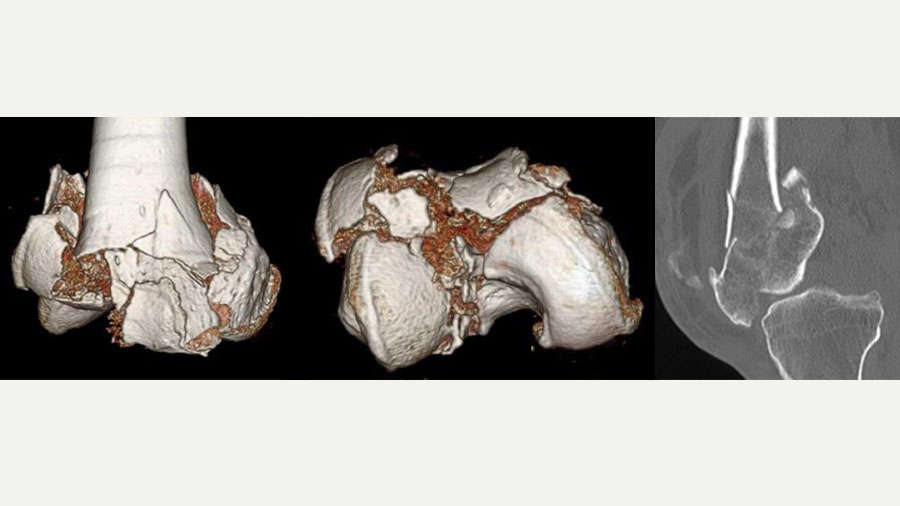

A 58-year-old farmer, the patient had always been physically active despite some age-related degenerative changes in his knees. His injury occurred from a fall in which he landed directly on his knee, resulting in a highly comminuted fracture. On initial inspection, the fracture resembled a shattered stone, with seven to eight individual fragments within the knee joint. These fragments included articular surfaces critical for knee function, making the restoration of joint congruity both urgent and exceptionally challenging.

The complexity of the injury required a structured, multi-step approach, starting with comprehensive imaging. While X-rays provided an initial overview, it was the CT scan that delivered the critical 3D visualization of the fracture pattern. This enabled precise identification of each fragment and helped enormously in preoperative planning.

Such advanced imaging is essential for joint injuries where the accuracy of reduction dictates functional outcome. It allowed me to mentally reconstruct the knee and consider the tools and implants I would need. A detailed plan was then developed with contingencies in place—Plan B, and Plan C etc—including alternatives for fixation devices that might not conform to standard knee fracture patterns.